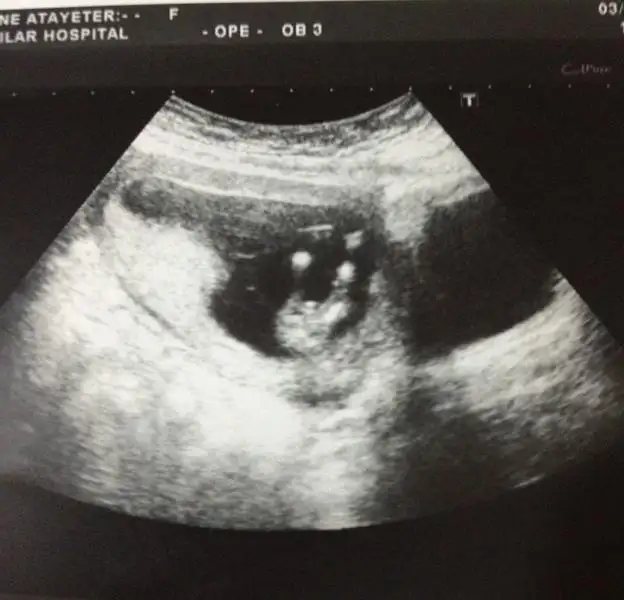

herkese merhaba, bebeğim burada tam 12 haftalık. ikili test için gittiğimde alındı bu görüntü. doktor %50 kız %50 erkek dedi sağolsun. buradan okuduklarım kadarıylada nub göremedim sanki bacak arasında kalmış gibi geldi. çok da merak eiyorum. yorumlarınızı bekliyorum. Eki Görüntüle 976147